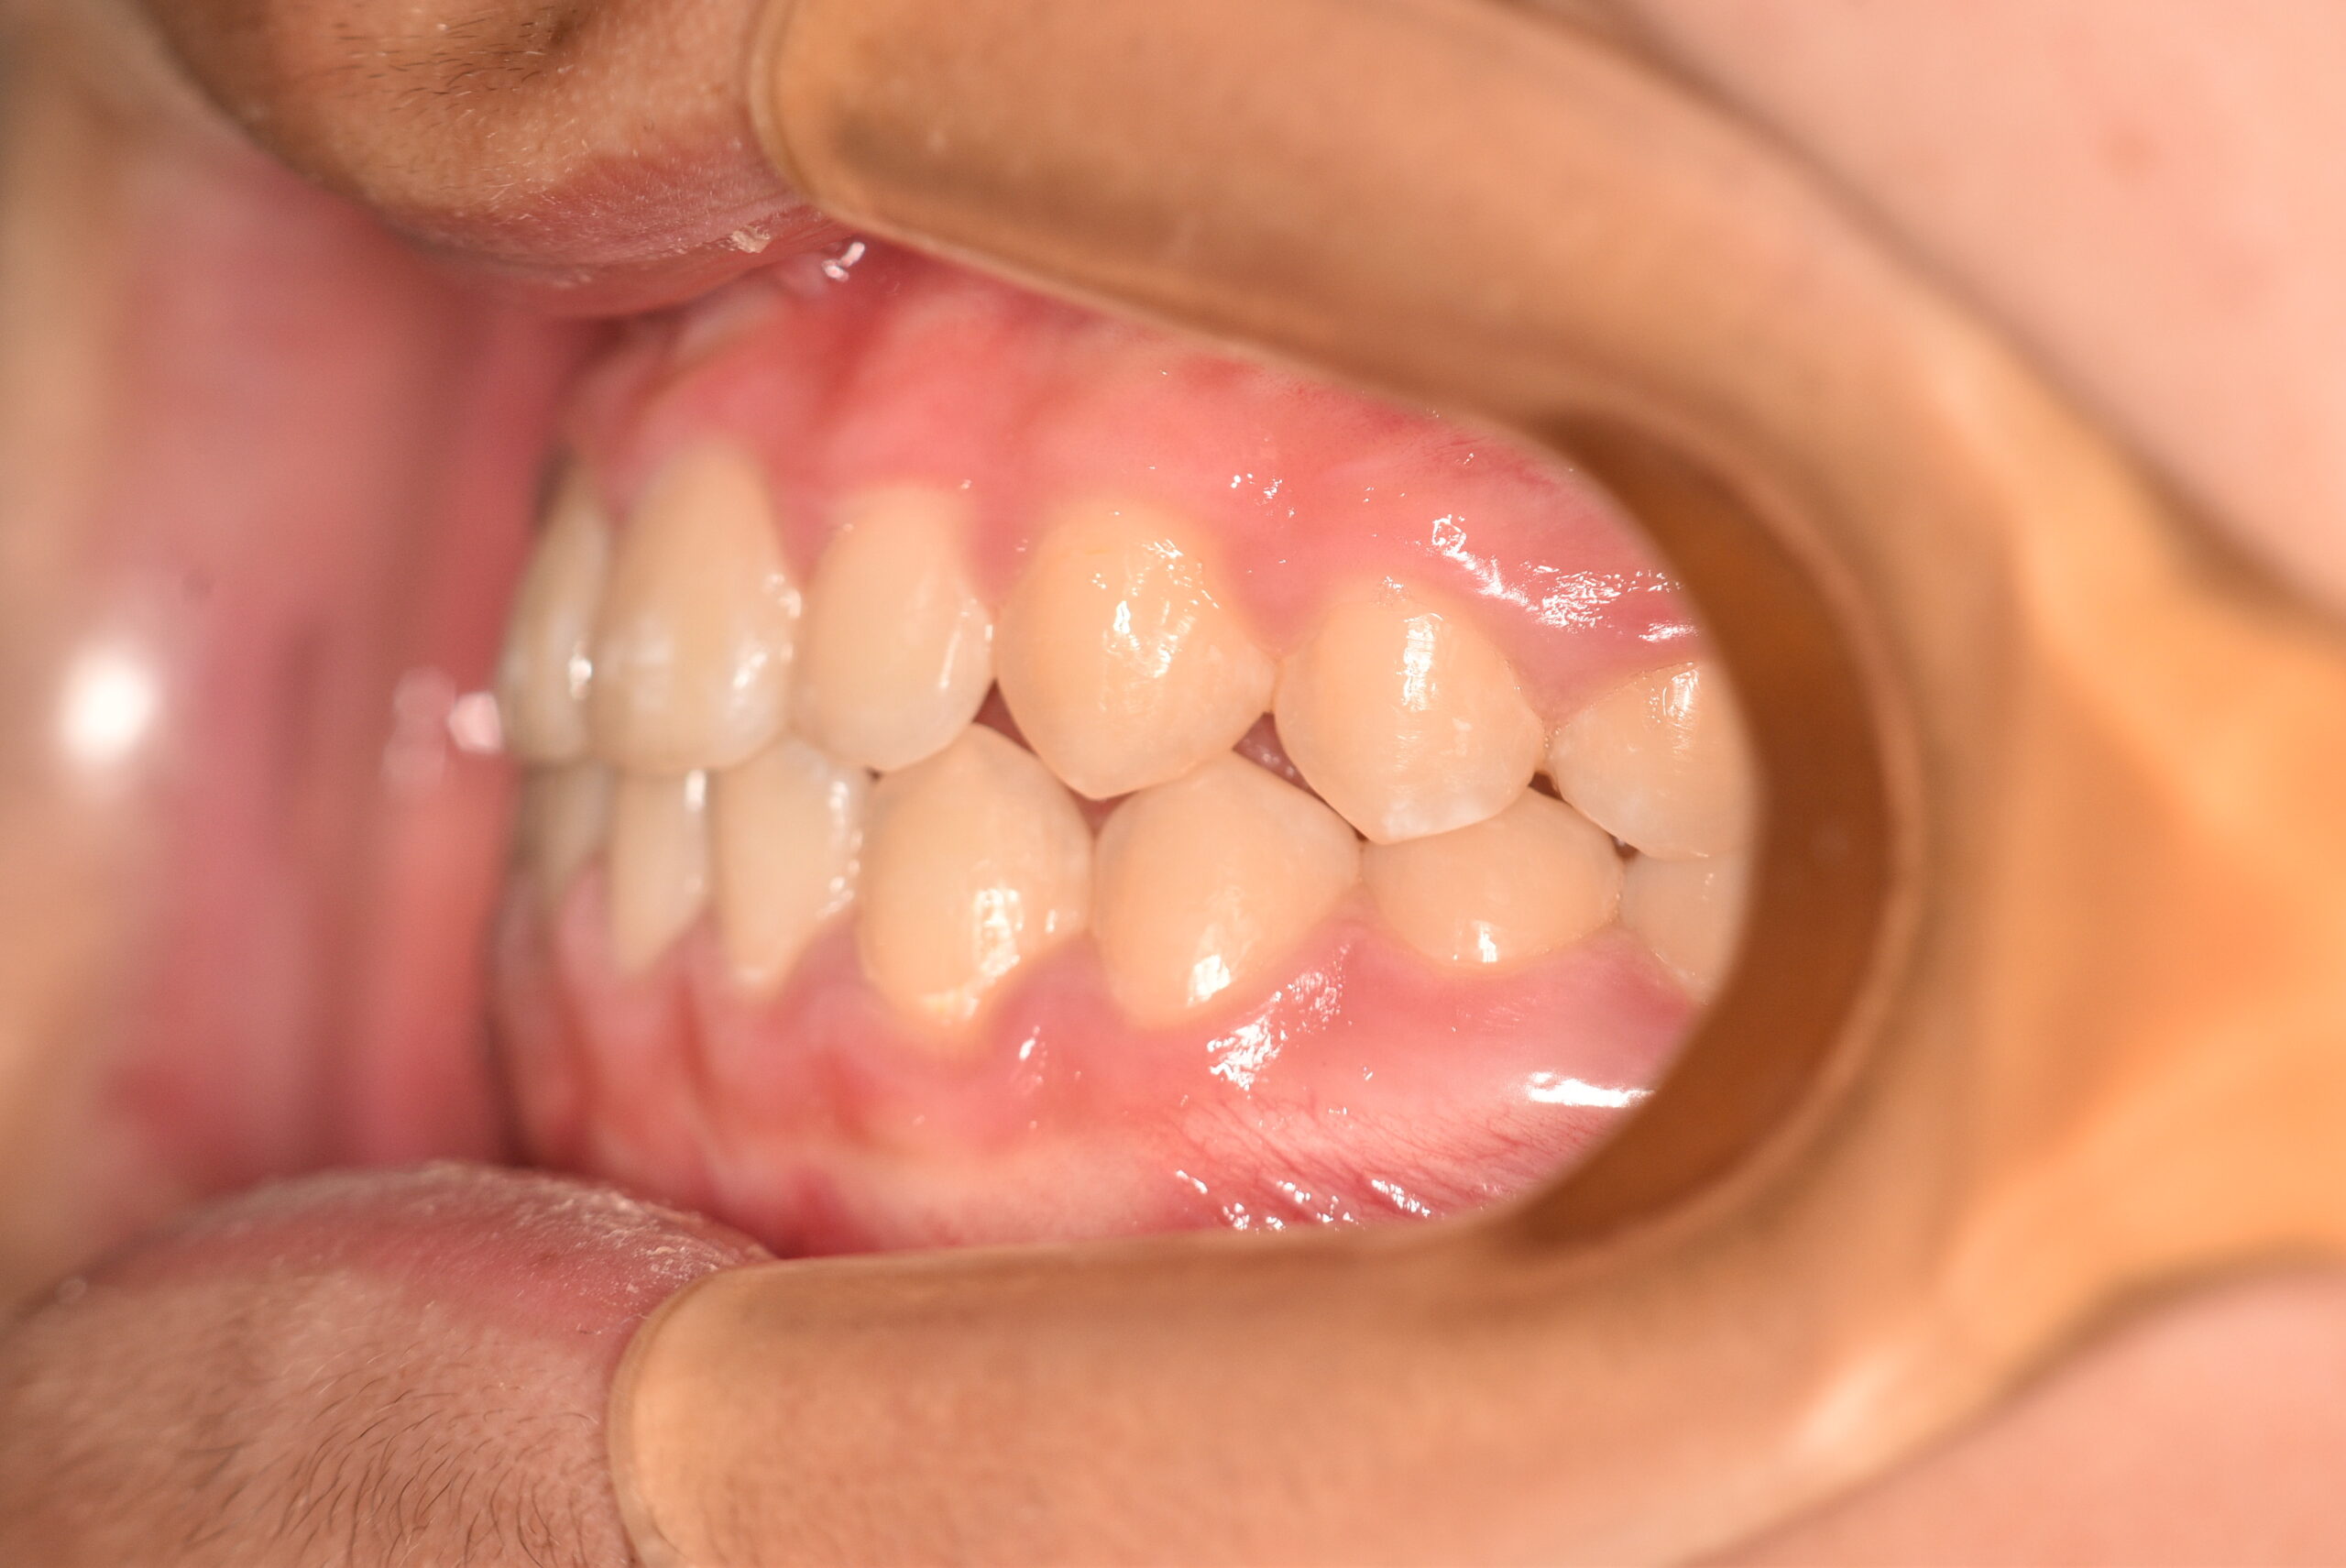

| 治療内容の詳細 | 初診時6歳の男性で、受け口を気にされ来院されました。 検査の結果、反対咬合を伴うアングルⅢ級不正咬合と診断しました。 治療としては、初期段階の治療として、機能的矯正装置で鼻呼吸の獲得と舌の位置や口唇の閉鎖といった筋機能習癖の改善を行い、上顎前方牽引装置を使用し上顎骨の前方方向への発育を誘導し、反対咬合の改善を行いました。 永久歯列に交換後、非抜歯の上、セルフライゲーションブラケット装置(デーモンシステム)で歯の配列と咬合関係の改善を行いました。 治療期間は、7年3ヶ月でした。 |